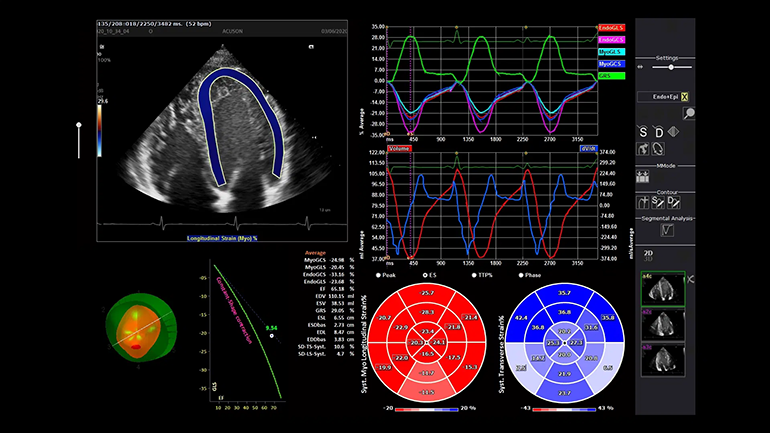

Векторный анализ кардиомиокинетики (syngo Velocity Vector Imaging). syngo Velocity Vector Imaging поддерживает оценку глобальной и региональной механики движения сердечной мышцы, включая глобальную продольную деформацию.Рабочий процесс

Технология выполнения измерений левых отделов сердца (eSie Left Heart). Пакет измерений левых отделов сердца eSie Left Heart — это надежный инструмент, который повышает надежность и оптимизирует рабочий процесс благодаря автоматическому определению границ левого желудочка и левого предсердия и выполнению измерений при стандартных трансторакальных исследованиях у взрослых пациентов.

Технология выполнения измерений левых отделов сердца (eSie Left Heart). Пакет измерений левых отделов сердца eSie Left Heart — это надежный инструмент, который повышает надежность и оптимизирует рабочий процесс благодаря автоматическому определению границ левого желудочка и левого предсердия и выполнению измерений при стандартных трансторакальных исследованиях у взрослых пациентов. Технология автоматического исследования фолликулов (syngo ® Auto Follicle). В технологии syngo ® Auto Follicle реализован автоматический метод измерений, обеспечивающий быструю и точную оценку фолликулов. Автоматическое выполнение измерений и запись результатов помогают сократить продолжительность исследования.

Технология автоматического исследования фолликулов (syngo ® Auto Follicle). В технологии syngo ® Auto Follicle реализован автоматический метод измерений, обеспечивающий быструю и точную оценку фолликулов. Автоматическое выполнение измерений и запись результатов помогают сократить продолжительность исследования. Автоматизация процесса измерений (eSie Measure). Технологя eSie Measure предназначена для ускорения рабочего процесса благодаря полуавтоматическому выполнению измерений при стандартных эхокардиографических исследованиях, например. Это повышает эффективность работы и согласованность результатов для врачей-диагностов.

Автоматизация процесса измерений (eSie Measure). Технологя eSie Measure предназначена для ускорения рабочего процесса благодаря полуавтоматическому выполнению измерений при стандартных эхокардиографических исследованиях, например. Это повышает эффективность работы и согласованность результатов для врачей-диагностов. Технология автоматического измерения основных биометрических показателей плода (syngo ® Auto OB). syngo ® Auto OB реализован инновационный алгоритм распознавания анатомических ориентиров для шести стандартных измерений плода: CRL — копчико-теменной размер, BPD — бипариетальный размер головы, HL — длина плечевой кости, HC — окружность головы, AC — окружность живота и FL — длина бедренной кости. Благодаря этому все перечисленные измерения можно выполнить автоматически, одним нажатием функциональной кнопки.